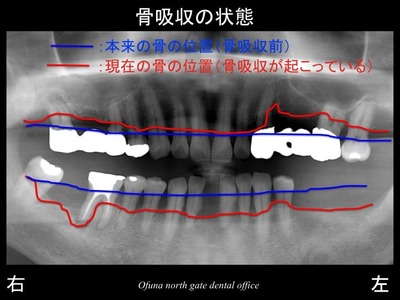

それでは骨吸収の状態を見てみましょう!

いつものように 骨吸収の状態を分かりやすくするために

骨吸収の状態を線で書いたのが以下のレントゲンになります。

青線が骨吸収を起こす前の骨の位置です。

赤線は、現在の骨の位置です。

かなりの骨吸収が起こっているのが分かるかと思います。